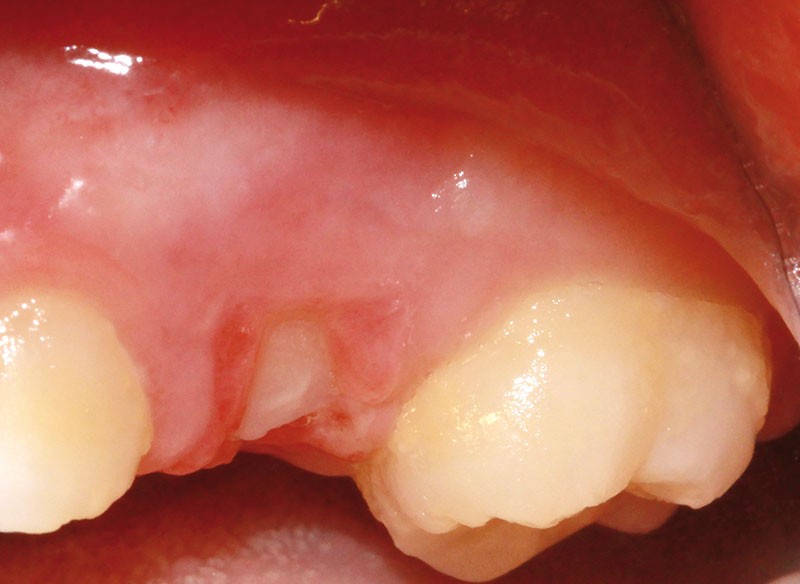

L’examen clinique révèle la présence d’une ulcération végétante, d’environ 1 cm de diamètre, localisée sur les gencives marginale, papillaire et attachée en vestibulaire de 55 et 16, associée à une récession parodontale pour 55. L’ulcération est bien délimitée, indolore et non hémorragique spontanément. Les dents présentent une mobilité physiologique et il n’existe pas d’adénopathie.